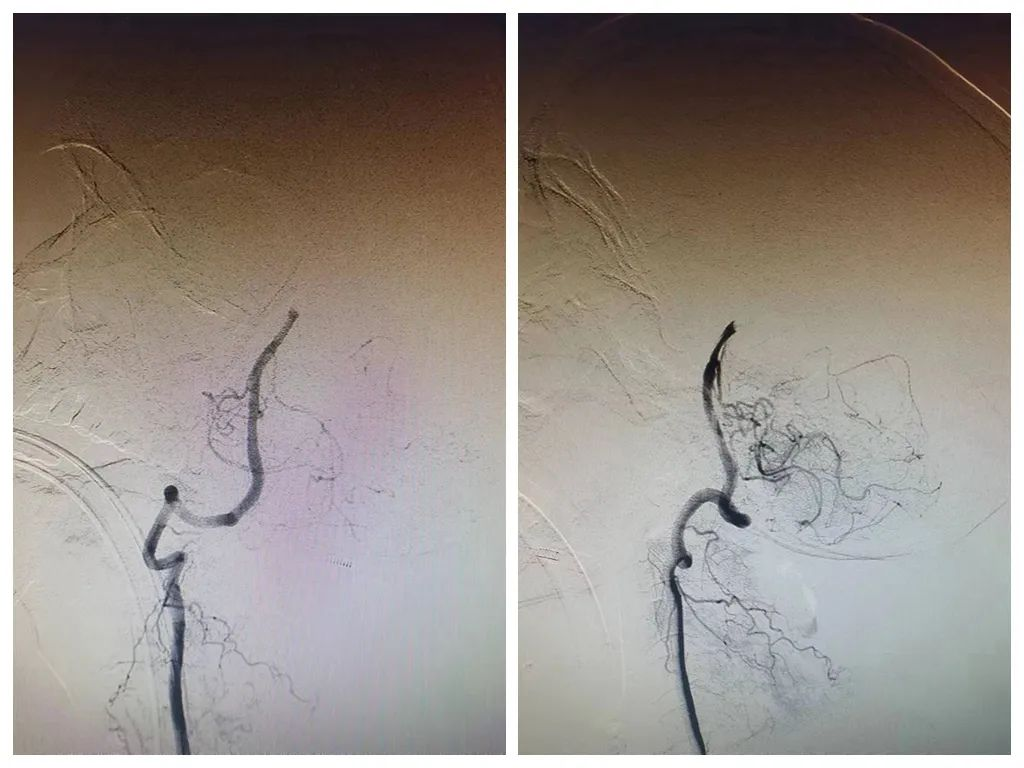

术前造影

术后造影

3:30分,张先生在急诊局麻+镇静下进行了全脑血管造影术+血栓抽吸术,造影显示:基底动脉远端显影,前向血流3级,右侧大脑后P1段闭塞,考虑栓子逃逸,左侧大脑后动脉远端未见明显血栓栓塞,沿8F导引导管缓慢注入尿激酶10万单位,手术过程非常顺利,术后复查颅脑CT后安全返回病房。